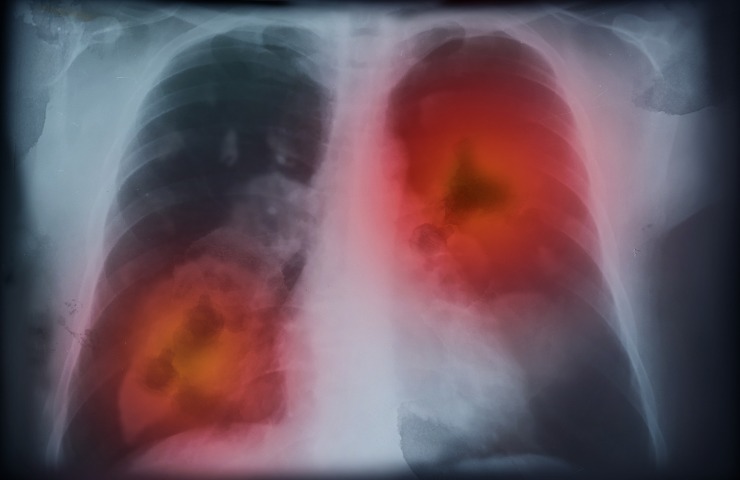

Il tumore ai polmoni è tra le malattie più temibili che ci siano. La principale causa di tale, spaventosa e spesso inesorabile malattia è da attribuire soprattutto all’abuso di fumo. Le conseguenze per i polmoni sono tremende, in tal caso. Ma arriva notizia di un progresso che può essere davvero molto significativo nel concreto per quanto concerne proprio la lotta al tumore ai polmoni. E grazie a dei ricercatori che hanno segnato un passo importante proprio da noi, in Italia.

Si parla infatti di una terapia a bersaglio molecolare per trattare ed eliminare il carcinoma polmonare a non a piccole cellule (NSCLC) Alk-positivo con rischio elevato di recidività. Ed è la prima situazione di sempre in questo senso, relativamente alle terapie a bersaglio. Per terapia a bersaglio si intende un percorso in ambito terapeutico che ha come scopo quello di colpire specifiche componenti, come proteine o molecole malate. Proprio queste sono le responsabili del sorgere e del proliferare di cellule di tumori di vario tipo.

Sono diverse le forme di tumore ai polmoni, e tra queste spicca proprio il carcinoma polmonare Alk-positivo, che è tra quelle più rare e tende a colpire soggetti giovani persino non fumatori. In media la speranza di vita per questa malattia, a prescindere dalle sue tipologie, va dai dieci ai quattordici mesi.

Il farmaco ricavato è capace di abbassare di ben il 76% il pericolo recidività e di morte, se i suoi effetti vengono confrontati con gli effetti della chemioterapia al platino, che rappresenta la cura standard. Tutto ciò è stato notato in pazienti ai quali il farmaco – chiamato alectinib – è stato sottoposto, e tutti loro si trovavano in una fase iniziale di tumore.

Tale farmaco riduce sensibilmente pure il diffondersi di metastasi, soprattutto nell’area cerebrale.

Ora si ha a disposizione in tutto e per tutto una terapia mirata contro questa forma di malattia, ed è una ottima notizia visto che, anche intervenendo in maniera precoce, il pericolo recidiva è sempre stato alto.